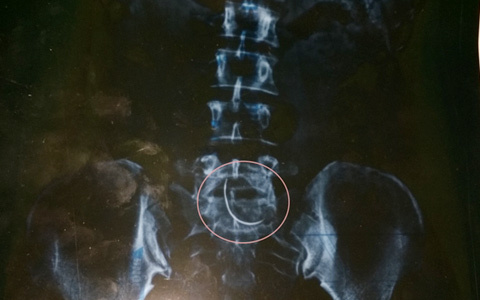

- Mổ đẻ, BS ‘quên’ kim trong bụng bệnh nhân 9 năm:

| Hình ảnh chiếc kim khâu trong bụng bệnh nhân |

Trong suốt nhiều năm kể từ sau lần mổ đẻ tại BVĐK huyện Can Lộc (Hà Tĩnh), chị Hòa thường bị đau đầu, bụng, huyết áp cao. Trong một lần đi chụp X-quang, chị Hòa choáng váng khi biết, dưới vết mổ cũ trong bụng có 1 chiếc kim khâu mà bác sĩ để "quên" 9 năm nay.